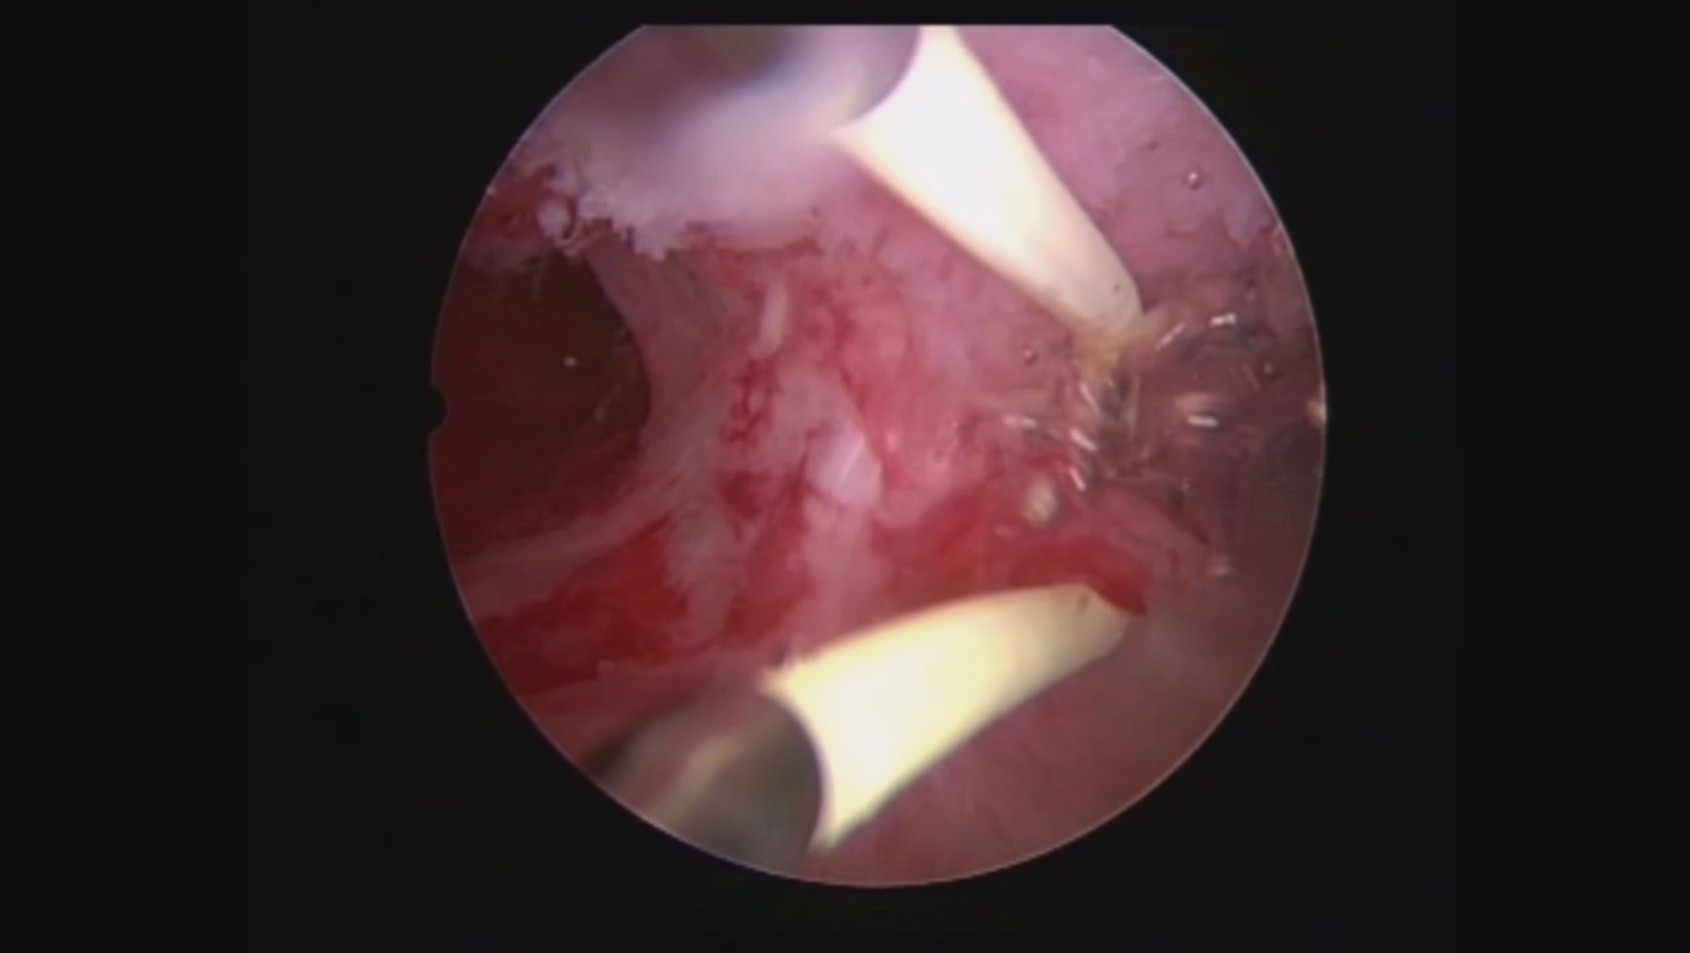

患者32岁,G6P0,继发不孕,2017年8月行宫腔镜探查,发现宫腔两侧及宫底致密粘连,尤其是宫腔右侧多重粘连,宫腔狭小。单极电切分粘,恢复宫腔形态,显露双侧输卵管开口。2018年8月自然妊娠40多天,我在兰州大学附一院生殖中心进修,病人微信发B超给我,大孕囊,胎心微弱,外院疑诊胚胎停育,拟行清宫,嘱病人不要轻易清宫,继续保胎1周,复查B超,胚胎发育正常。病人的信心和坚持成就了她自己和孩子的奇迹,孕期顺利,足月分娩。后病人再次妊娠1次,人流终止妊娠,现41岁,G8P1。